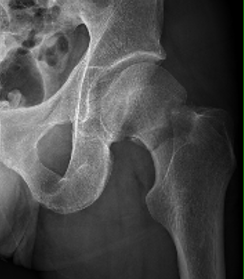

Haidukewych et al JBJS Am 2004

- 51 displaced subcapital fractures < 50

- 10% incidence of nonunion

- 27% osteonecrosis

- nonunion 4% with good to excellent reduction

- nonunion 80% with poor reduction (>10 mm of displacement, >20°, any varus)

Assessment of reduction

1. Femoral neck shaft angle

2. Restoration of Shenton's line